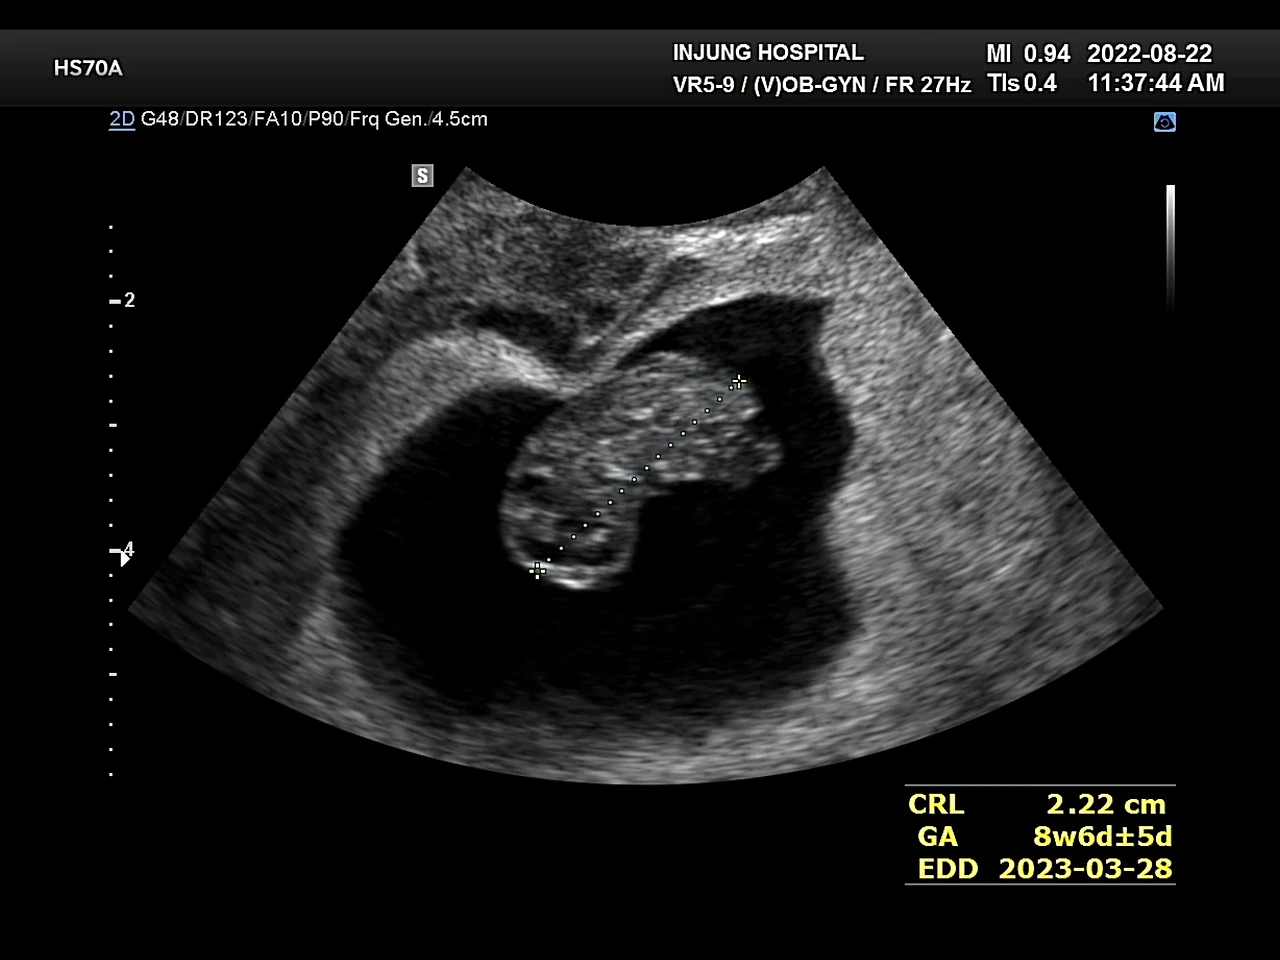

8주

아인이에게 임신 소식을 알렸다. 듣자마자 거짓말하지 말라는 아인이. 초음파 사진을 보여주면서 진지하게 한번 더 얘기해주자 눈물을 펑펑 터트렸다. 아인이는 동생이 늦게 태어났으면 좋겠다고 했다. 평소에도 동생은 필요 없다고 말해왔기도 하고, 어린이집에서도 자기보다 한참 어린 친구들에게는 전혀 관심이 없어서 기뻐하진 않을 거라는 것 정도는 예상했다. 그런데 이 정도로 싫어할 줄이야. 아인이를 겨우 달래서 문구점에 가서 좋아하는 스티커를 사주었다. 평소와 달리 크게 좋아하지 않아서 더 마음이 쓰였다.